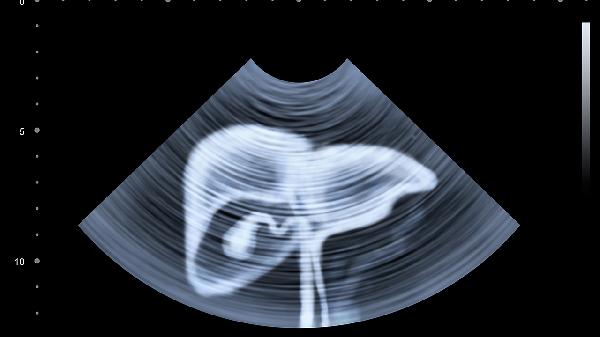

肝脏彩色多普勒超声通常需要空腹进行,但部分情况下可无须空腹。该检查主要用于评估肝脏血流状态及结构异常,空腹能减少胃肠内容物干扰,提高图像清晰度。

常规肝脏彩色多普勒超声检查要求空腹8-12小时。空腹状态下胆囊充盈良好,胃肠气体减少,有利于观察肝内血管走行及血流信号。进食后胆汁排空可能导致胆囊收缩显影不清,高脂饮食可能增加血液黏稠度影响血流参数测量。胃内食物残渣或气体可能遮挡肝左叶显像,尤其肥胖或肠胀气患者更需严格空腹。